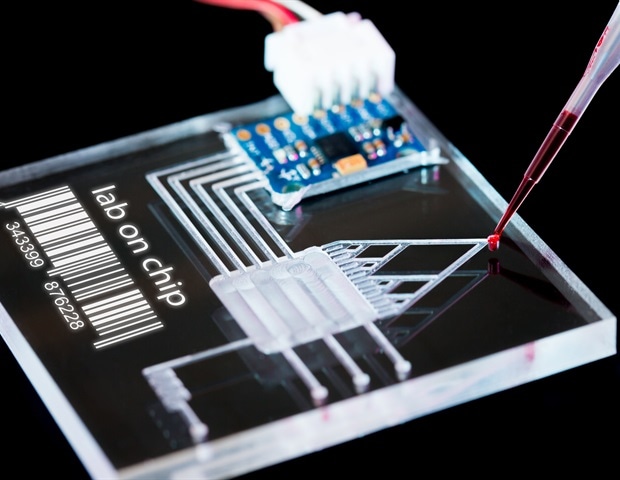

Sphere Fluidics, ספקית מובילה של פתרונות מיקרופלואידיקה חדשניים מבוססי טיפות ליצירת פרופיל פונקציונלי של תאים בודדים בקנה מידה, הודיעה היום

CN Bio, ספקית מובילה של מערכות איבר-על-שבב ופתרונות המאיצים את תהליכי העבודה של גילוי ופיתוח תרופות, הודיעה היום על השקת